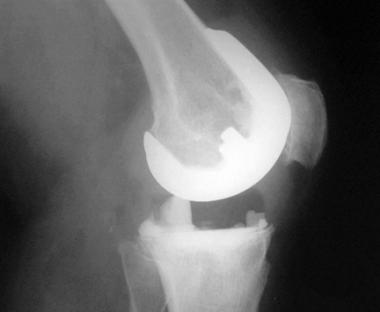

In late infections, complete removal of the prosthesis, along with all components and cement, is indicated. Measurements of ESR and CRP level are important for diagnosis of chronic infection. Usually, revision of the components is required. A two-stage revision is best. A postoperative temporary (first-stage) insert can be seen in the image below. It is important to excise all infected tissue; this requires a complete synovectomy and a thorough washout with at least 10 L of isotonic sodium chloride solution.

Complications of total knee arthroplasty. Postoperative temporary insert.